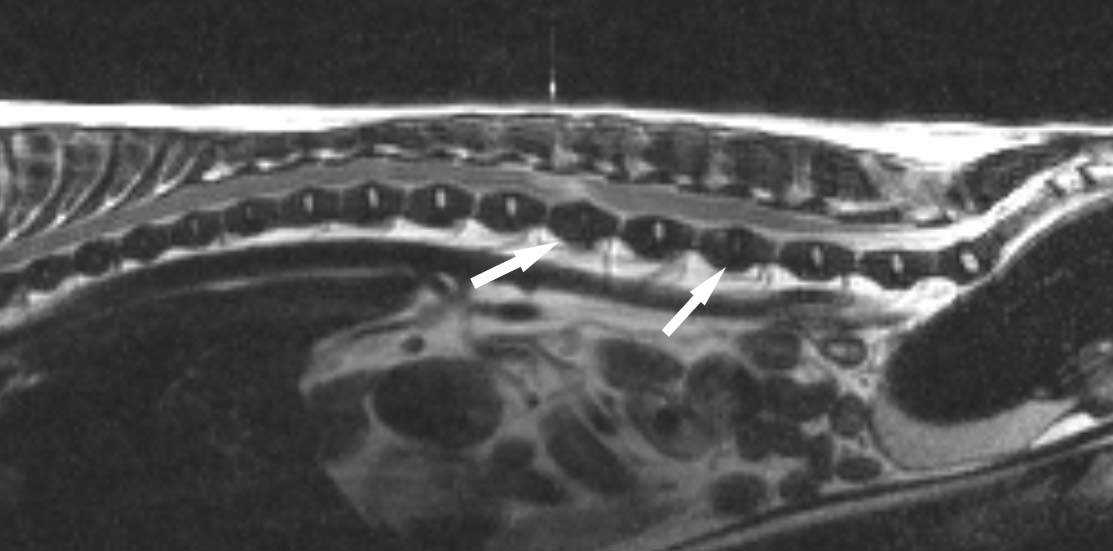

Самым информативным методом диагностики болезней межпозвонковых дисков являются МРТ или КТ. Данные исследования более точные и при этом неинвазивные.

МРТ диагностика при заболевании межпозвонковых дисков позволяет лучше увидеть травму или любые другие последствия выпадения грыжи или длительной компрессии спинного мозга. С помощью МРТ-диагностики можно распознать раннюю дегенерацию межпозвонкового диска: в режиме Т2 диск будет иметь снижение интенсивности сигнала — диск будет тёмным. Выпавшее содержимое диска в режиме Т2 в просвете спинномозгового канала будет так же темным, а впоследствии выпадения грыжи — отёк, некроз или воспаление будут иметь гиперинтенсивный сигнал. С помощью МРТ-диагностики можно оценить прогноз на выздоровление: если гиперинтенсивный сигнал от спинного мозга равен или больше длинны тела L2 (второго поясничного позвонка), то прогноз на восстановление составляет 55%, а с потерей глубокой болевой чувствительности всего лишь 10%.